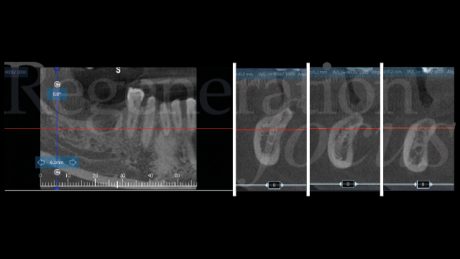

Una paziente di 44 anni, non fumatrice e in buone condizioni di salute generale, si è presentata riferendo significative difficoltà masticatorie, nel quarto quadrante, conseguenti alla perdita del ponte 45-47 per complicanze endodontico-protesiche. L’anamnesi medica non rivelava patologie sistemiche di rilievo né assunzione di farmaci che potessero interferire con i processi di guarigione ossea. L’esame intraorale evidenziava una discreta atrofia della cresta alveolare edentula con collasso vestibolo-linguale dei tessuti molli (Fig. 1). Gli elementi dentari adiacenti presentavano condizioni parodontali stabili. L’analisi radiografica tridimensionale, mediante CBCT, ha permesso una valutazione dettagliata del deficit osseo (Fig. 2). Dopo discussione delle diverse opzioni terapeutiche, inclusa la possibilità di impianti corti, si è optato per una rigenerazione ossea guidata mediante mesh customizzata.

La pianificazione digitale ha guidato il design di una mesh patient-specific (Yxoss CBR® Protect) con spessore 0.6 mm, perforazioni di 1.2 mm, estensione 3 mm oltre i margini del difetto (Fig. 3).